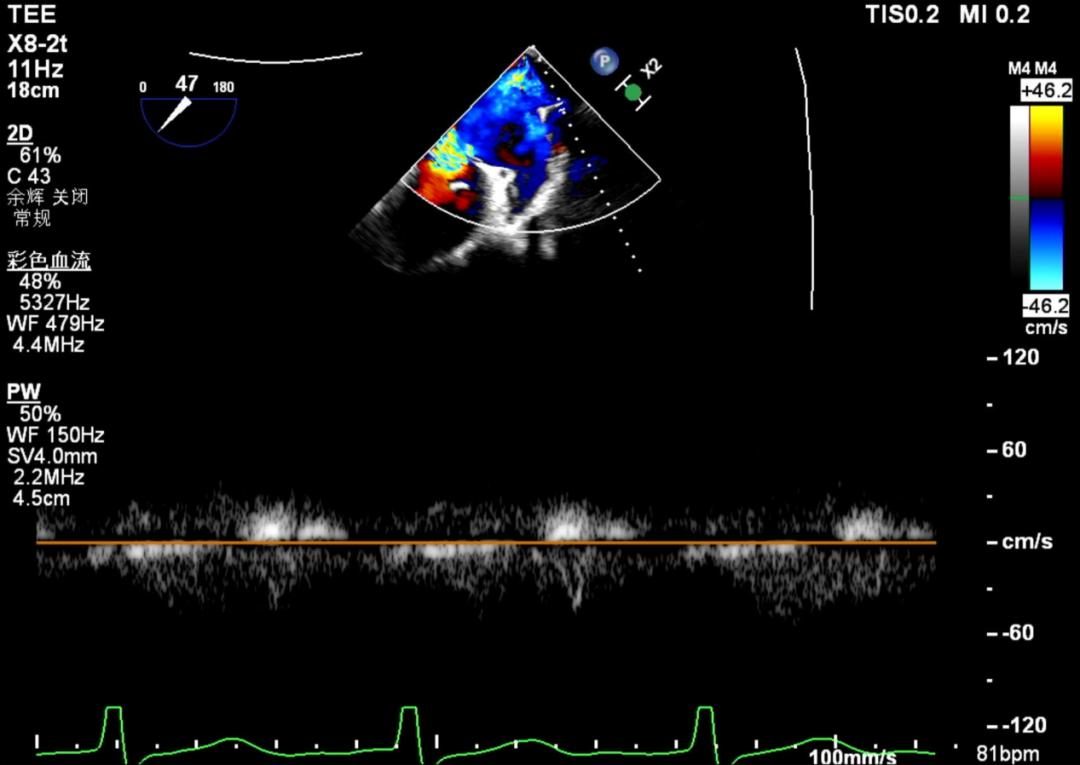

术前TEE评估

术前瓣膜介入团队的心超医生陈星星医师王良国医师对患者的心脏结构和瓣膜解剖情况进行详细的评估:

1.二尖瓣重度关闭不全(4+),瓣环明显扩大(AP径4.6cm,LM径3.9cm),扁平,关闭时瓣叶对合不佳(carpentier I),1-3区均可见反流束,返流宽度达26mm;肺静脉频谱呈收缩期反向。

2.画迹法测得二尖瓣瓣口面积约8.8cm²。

3.PISA法测得EROA=0.57cm²,Rvol=77ml,r=11mm。

4.二尖瓣前叶(A2)长度29mm,后叶(P2)长度11mm。

5.左房巨大(三径86*84*114mm),右房巨大(内径114*86mm),CFI提示极重度三尖瓣反流,Teich法测得EF为70.1%。

术前肺静脉频谱